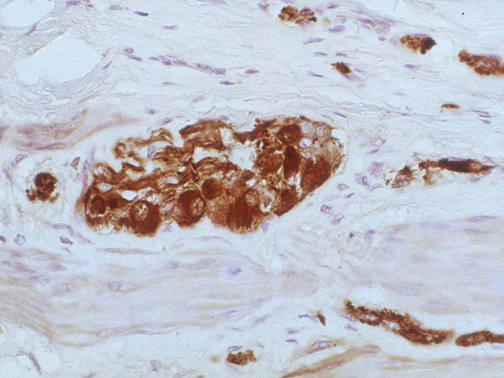

The submucosal plexuses with ganglia are seen here in the colon with immunohistochemical staining for S-100, a marker of neuronal differentiation. This stain also highlights small nerves .